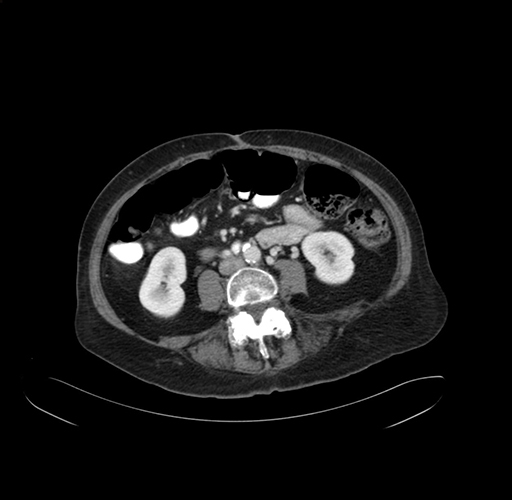

Axial Venous